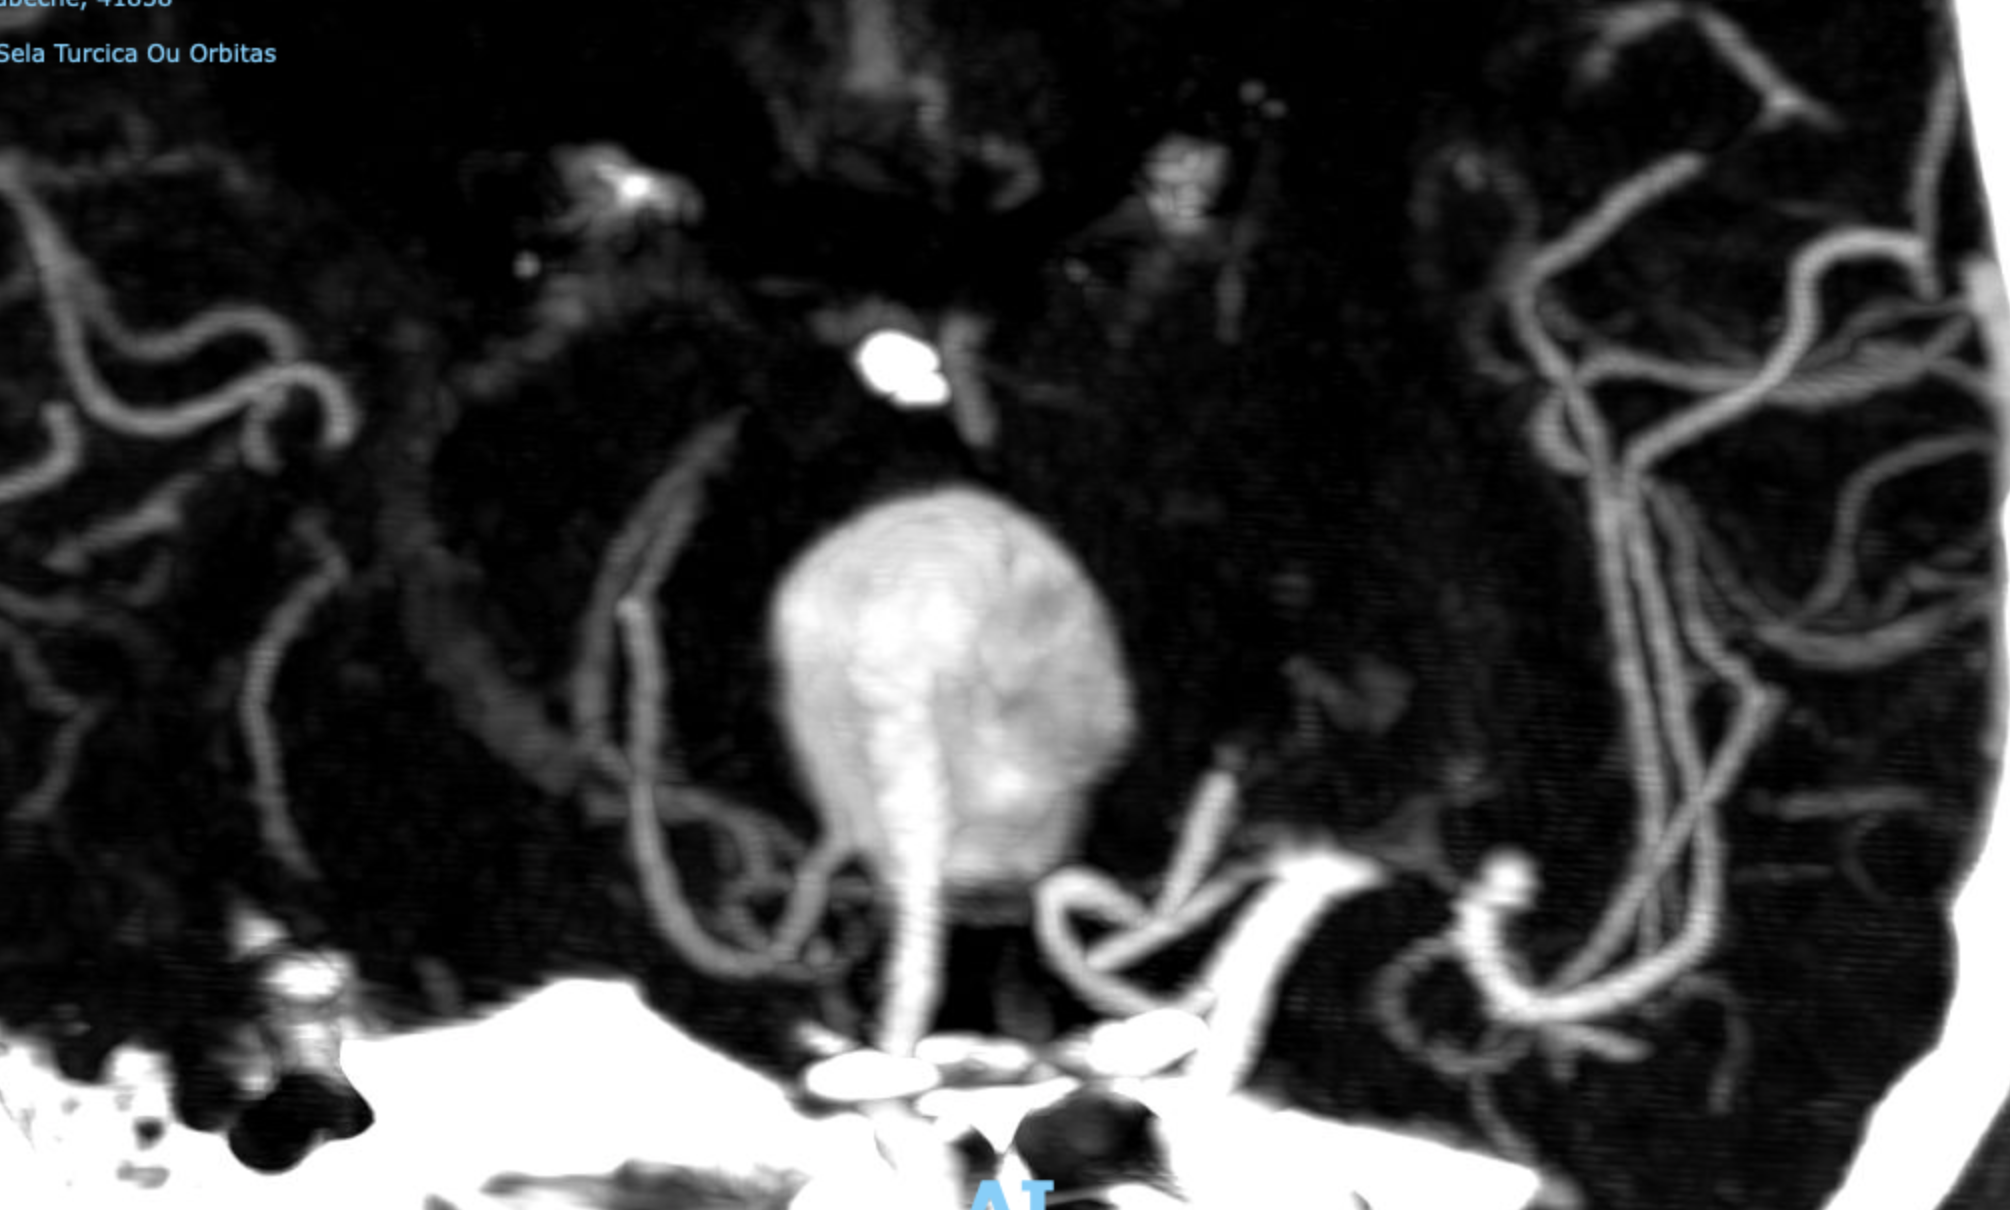

Um aneurisma gigante do topo da basilar é o nome técnico da doença que fez com que as pupilas ficassem de tamanhos diferentes. Essa condição chama-se anisocoria.

“Aneurismas cerebrais são dilatações anormais nas paredes dos vasos sanguíneos cerebrais. Suas causas e seu desenvolvimento podem ser congênitas ou adquiridas através de outros fatores como envelhecimento, pressão arterial elevada e tabagismo. O risco médio anual de ruptura é de 10 a 21 indivíduos a cada 100.000 pessoas. O prognóstico do paciente é pior após a ruptura e sangramento cerebral.”

O aneurisma dela estava localizado numa região do cérebro de difícil acesso, era grande demais e tinha um risco iminente de romper nas próximas semanas.